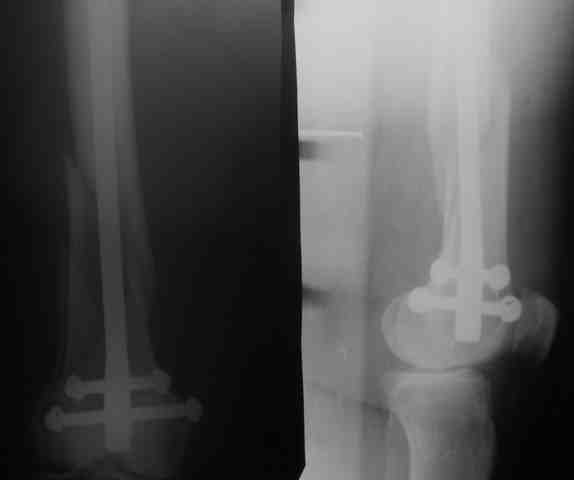

КАН> допущенные ошибки. Спасибо. Рг в приложении.

Снимки вполне симпатичные. Единственное, по ротации не понял, уж больно неразборчивый тот, который без гвоздя.